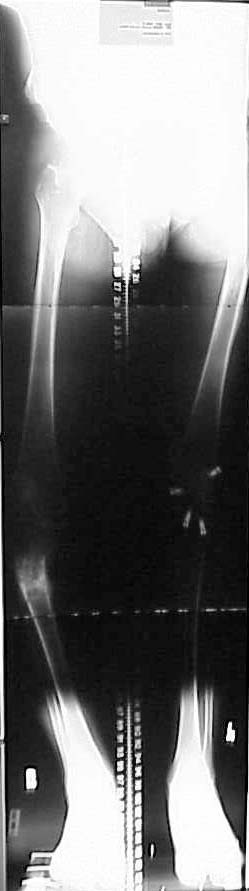

Thanks for the input on the tibia malunion w/ multiple plane deformity. I decided on a single cut osteotomy and IMN fixation based on desire to walk early, return to professor duties, and my previous experience w/ similar deformities (see another tibial malunion -below). The opening wedge was packed w/ a combination of autograft, allograft and demineralized bone.

Another tibial malunion -

Pt was 10 yrs s/p open tibia fx treated in a cast w/ IR, varus, 2 cm short, and recurvatum. He has done well post op.

preop

intraop

18 mos postop